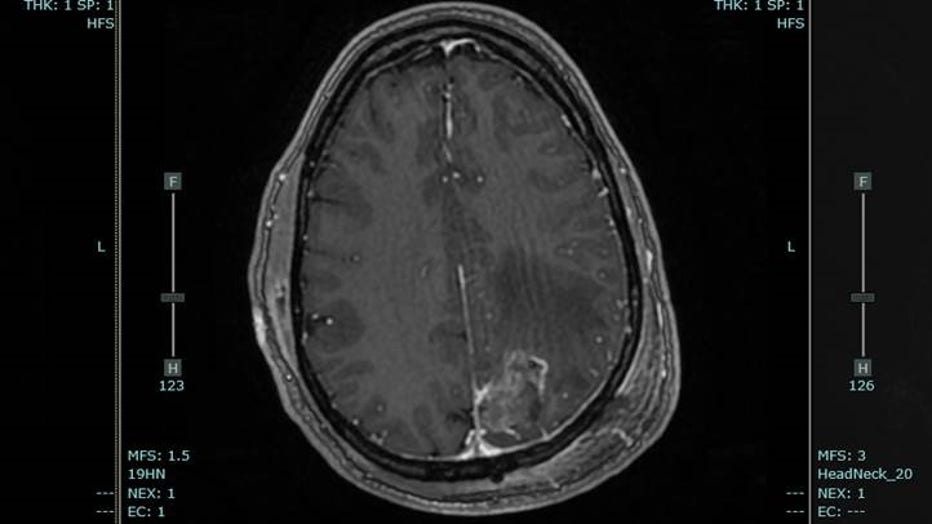

At Piedmont Atlanta Hospital, doctors found a golf ball-sized tumor in Neill's brain, a glioblastoma.

He gets MRIs every 8 weeks to track his progress.